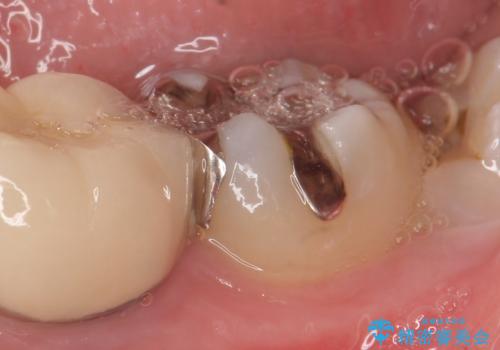

- 右下7の銀歯を白くしたいといらっしゃった方の症例です。

銀歯及び虫歯を除去後、セラミックインレーで修復を行いました。

当院のセラミックインレーはemaxという強度と審美性に優れた材料を使用しています。

またプレス方式でインレーを製作しているため、削り出しで製作するCADCAMより優れた適合性も持ち合わせており、虫歯が再発しにくい修復物です。